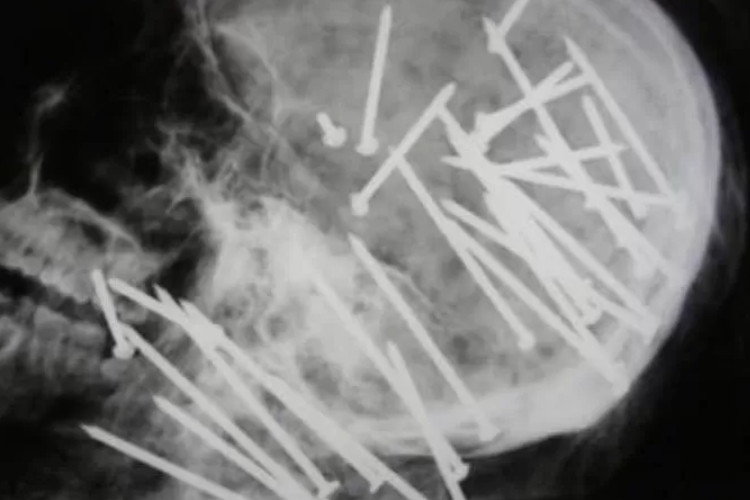

Gambar yang diduga merupakan hasil rontgen (X-ray) viral ini memperlihatkan tengkorak dengan banyak paku menancap diduga ini merupakan tengkorak pria bernama Chen Liu.

Di dalam foto tersebut sebanyak 34 paku tertancap di kepala yang memicu perdebatan sengit di kalangan pengguna internet mengenai keaslian gambar tersebut.

Unggahan pertama kali muncul melalui akun Threads @mo_ve1_on, yang membagikan hasil X-ray tengkorak Chen Liu dengan keterangan: “Ini bukan susuk ala Indomie ya, guys. Ini tengkorak Chen Liu, pria berusia 27 tahun yang ditemukan meninggal di rawa-rawa luar Sydney. Ia tewas setelah ditembak 34 kali menggunakan pistol paku bertenaga tinggi.”